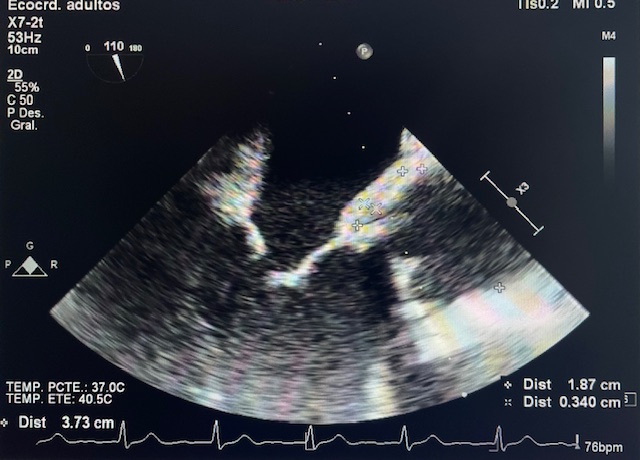

• ETT: lesión compatible con vegetación de 4-5 mm. En válvula protésica (imagen).

• TC Toracoabdominal: endocarditis complicada con absceso perivalvular.